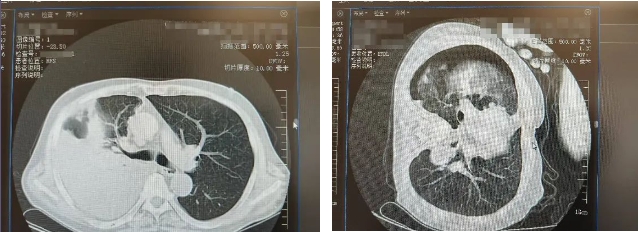

胸部CT结果显示右侧胸水

患者为男性,日前出现胸背部疼痛,并呈进行性加重,被家人紧急送至我院。患者有高血压等病史,考虑存在肋间神经痛,收治神经内科二病区。胸部CT检查结果显示:右侧大量胸腔积液并右肺实变、不张,医护人员迅速予以胸膜腔穿刺引流,引流出大量血性胸水。根据相关检查结果,不排除肿瘤。